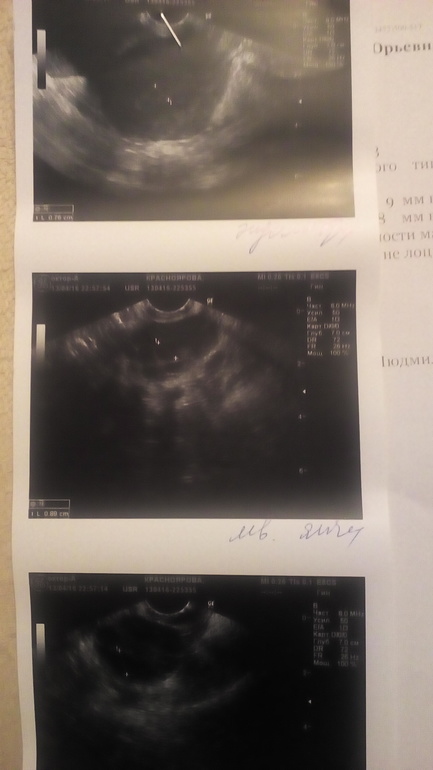

В этом месяце начала делать тесты на О с 8 дня цикла, так как месячные пришли на 21ДЦ. Думаю мало ли ранняя будет. В апетке были только Клевер (или как они там...). Читала что они ужасные, знаю, го нужно было израсхожовать пачку. На 13 ДЦ выдают довольно таки яркую очень тестовую полоску, почти такую же как и контрольную (фото снизу прилагаю, правда когда высохли бледные обе полоски стали). Я на радостях на след.день бегу на узи. И снова слышу заключение - ановуляторный цикл, ДФ отсутствует, самый большой всего 9.3мм, эндометрий 7.6мм. Опять расстороилась, но врач сказала на всякий случай продолжать делать тесты, вдруг чудо случится. Я тут же захожу в аптеку, покупаю овуплан любимый, прихожу домой и вот что

На утро повторяю не на первый попис (на фото тесты 15ДЦ подписаны) и полоски по цвету сравнялись. В течении дня кололо внизу живота и ооооочень много выделений типа ЯБ. Пришла с работы и сделала снова тест, он уже тускнее... (см.фото).

И вот вопрос - могла ли врач, делавшая узи ошибится и не найти ДФ?

У меня таких ярчайших тестов ч декабр не было!!!! Я просто не знаю что и думать. Снова сходить на фолликулометрию подтвердить? Когда лучше сходить?